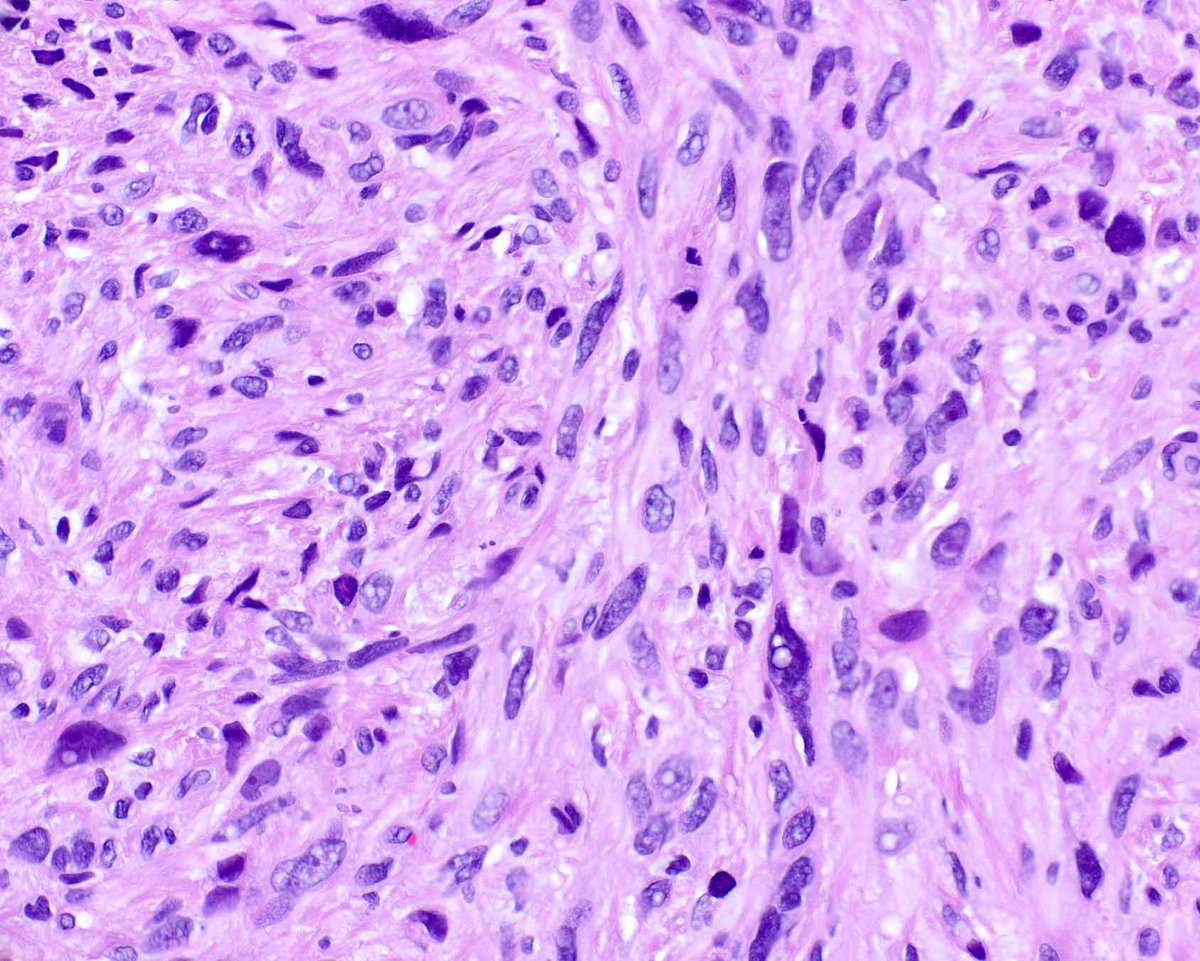

Please consider giving your pathology images a forever home on WebPathology. Now you can load them directly from the site using Submit Images form. Give it a try. Webpathology.com: A Collection of Surgical Pathology Images #PathTwitter #PathX